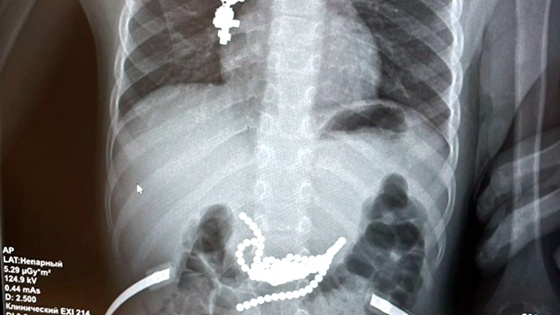

Мальчика отвезли в приемное отделение ГБУ РО "ОДКБ". Шарики были прекрасно видны на рентгеновском снимке. Проблема заключалась в том, что их нельзя было извлечь эндоскопом, так как посторонние предметы находились в подслизистом и мышечном слое желудка. Пришлось провести сложнейшую полосную операцию.

"Магниты были неодимовые, у них самая большая сила магнетизма, - приводятся в сообщении слова хирурга Антона Штарева. - В месте их стояния уже была предперфорация стенки желудка и 12-перстной кишки".

Основная часть магнитов находилась в желудке, а другие - в тонкой кишке. Чтобы достать все магниты, пришлось вскрывать просвет кишки и желудка. Если бы родители обратились в ОДКБ на пару часов позже, могла бы произойти перфорация, и тогда последствия для здоровья малыша были бы гораздо более тяжелыми.